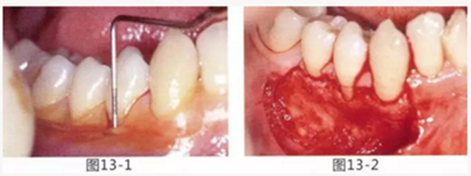

圖13-1 使用碘溶液進行染色,頰側基本看不到角化牙齦,且無口腔前庭的狀態(tài)。

圖13-2 為了擴張口腔前庭,獲取附著齦而進行了游離齦移植術。受皮床一定不能發(fā)生移動,盡可能使厚度均等。

圖13-3 手術剛結束的狀態(tài)。通過骨膜縫合的褥式縫合將移植片固定,使其無法移動。

圖13-4 手術完成2年后的狀態(tài)??谇磺巴サ玫綌U張,即使正在進行正畸治療,也沒有妨礙到清潔。